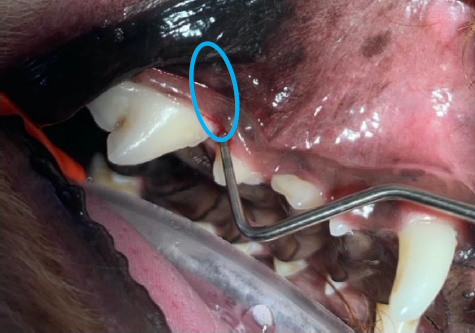

見た目は歯肉炎もなくキレイでしたが、歯周プローブを用いると一箇所だけ歯周プローブが入り込む場所がありました。その場所の歯科レントゲン検査を実施したところ、下記の写真のようになりました。

|

第4前臼歯の近心根の周囲の骨は歯周病により溶けてしまいました。歯根のまわりがどのようになっているかの評価に関しては、 CT 検査を実施するか、このような歯科レントゲン検査を実施しないと判断ができません。